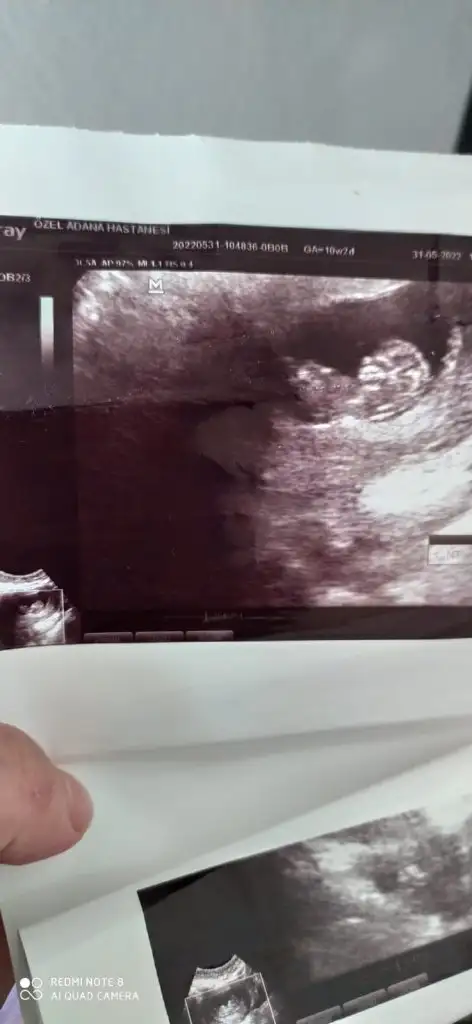

Yorumlar mısınız benımde karından 8 haftalık

• IMG-20220628-WA0001.webp

IMG-20220628-WA0001.webp

14,9 KB · Görüntüleme: 87